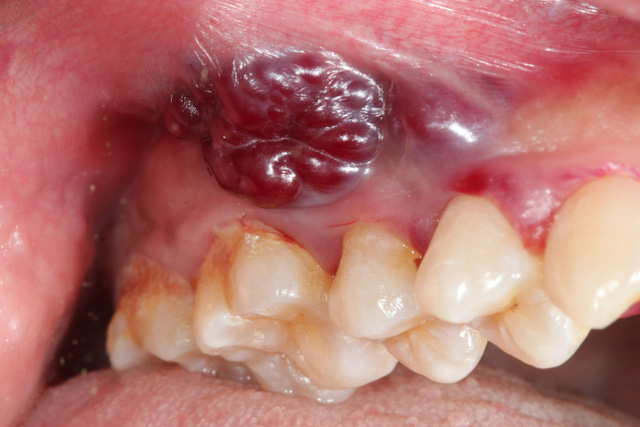

Trong những trường hợp thông thường, vết loét miệng sẽ dần lành từ 1-4 tuần. Tuy nhiên nếu là ung thư, vết loét sẽ không thể lành hay có bất kỳ dấu hiệu cải thiện nào trong suốt hơn 1 tháng. Hơn thế nữa, vết loét sẽ ngày càng lan rộng ra và đau đớn hơn, kèm các mạch máu sẽ hằn rõ.

Vết loét miệng bình thường sẽ nằm lộ rõ ra bên ngoài, có vết lõm sâu ở phần bị loét và phân biệt được bằng mắt thường. Thế nhưng nếu ung thư miệng bắt đầu phát triển, bạn sẽ khó phân biệt được đâu là phần da thịt lành và phần bị loét. Chưa kể có loại còn nằm sâu bên trong khoang miệng hoặc ẩn dưới da.